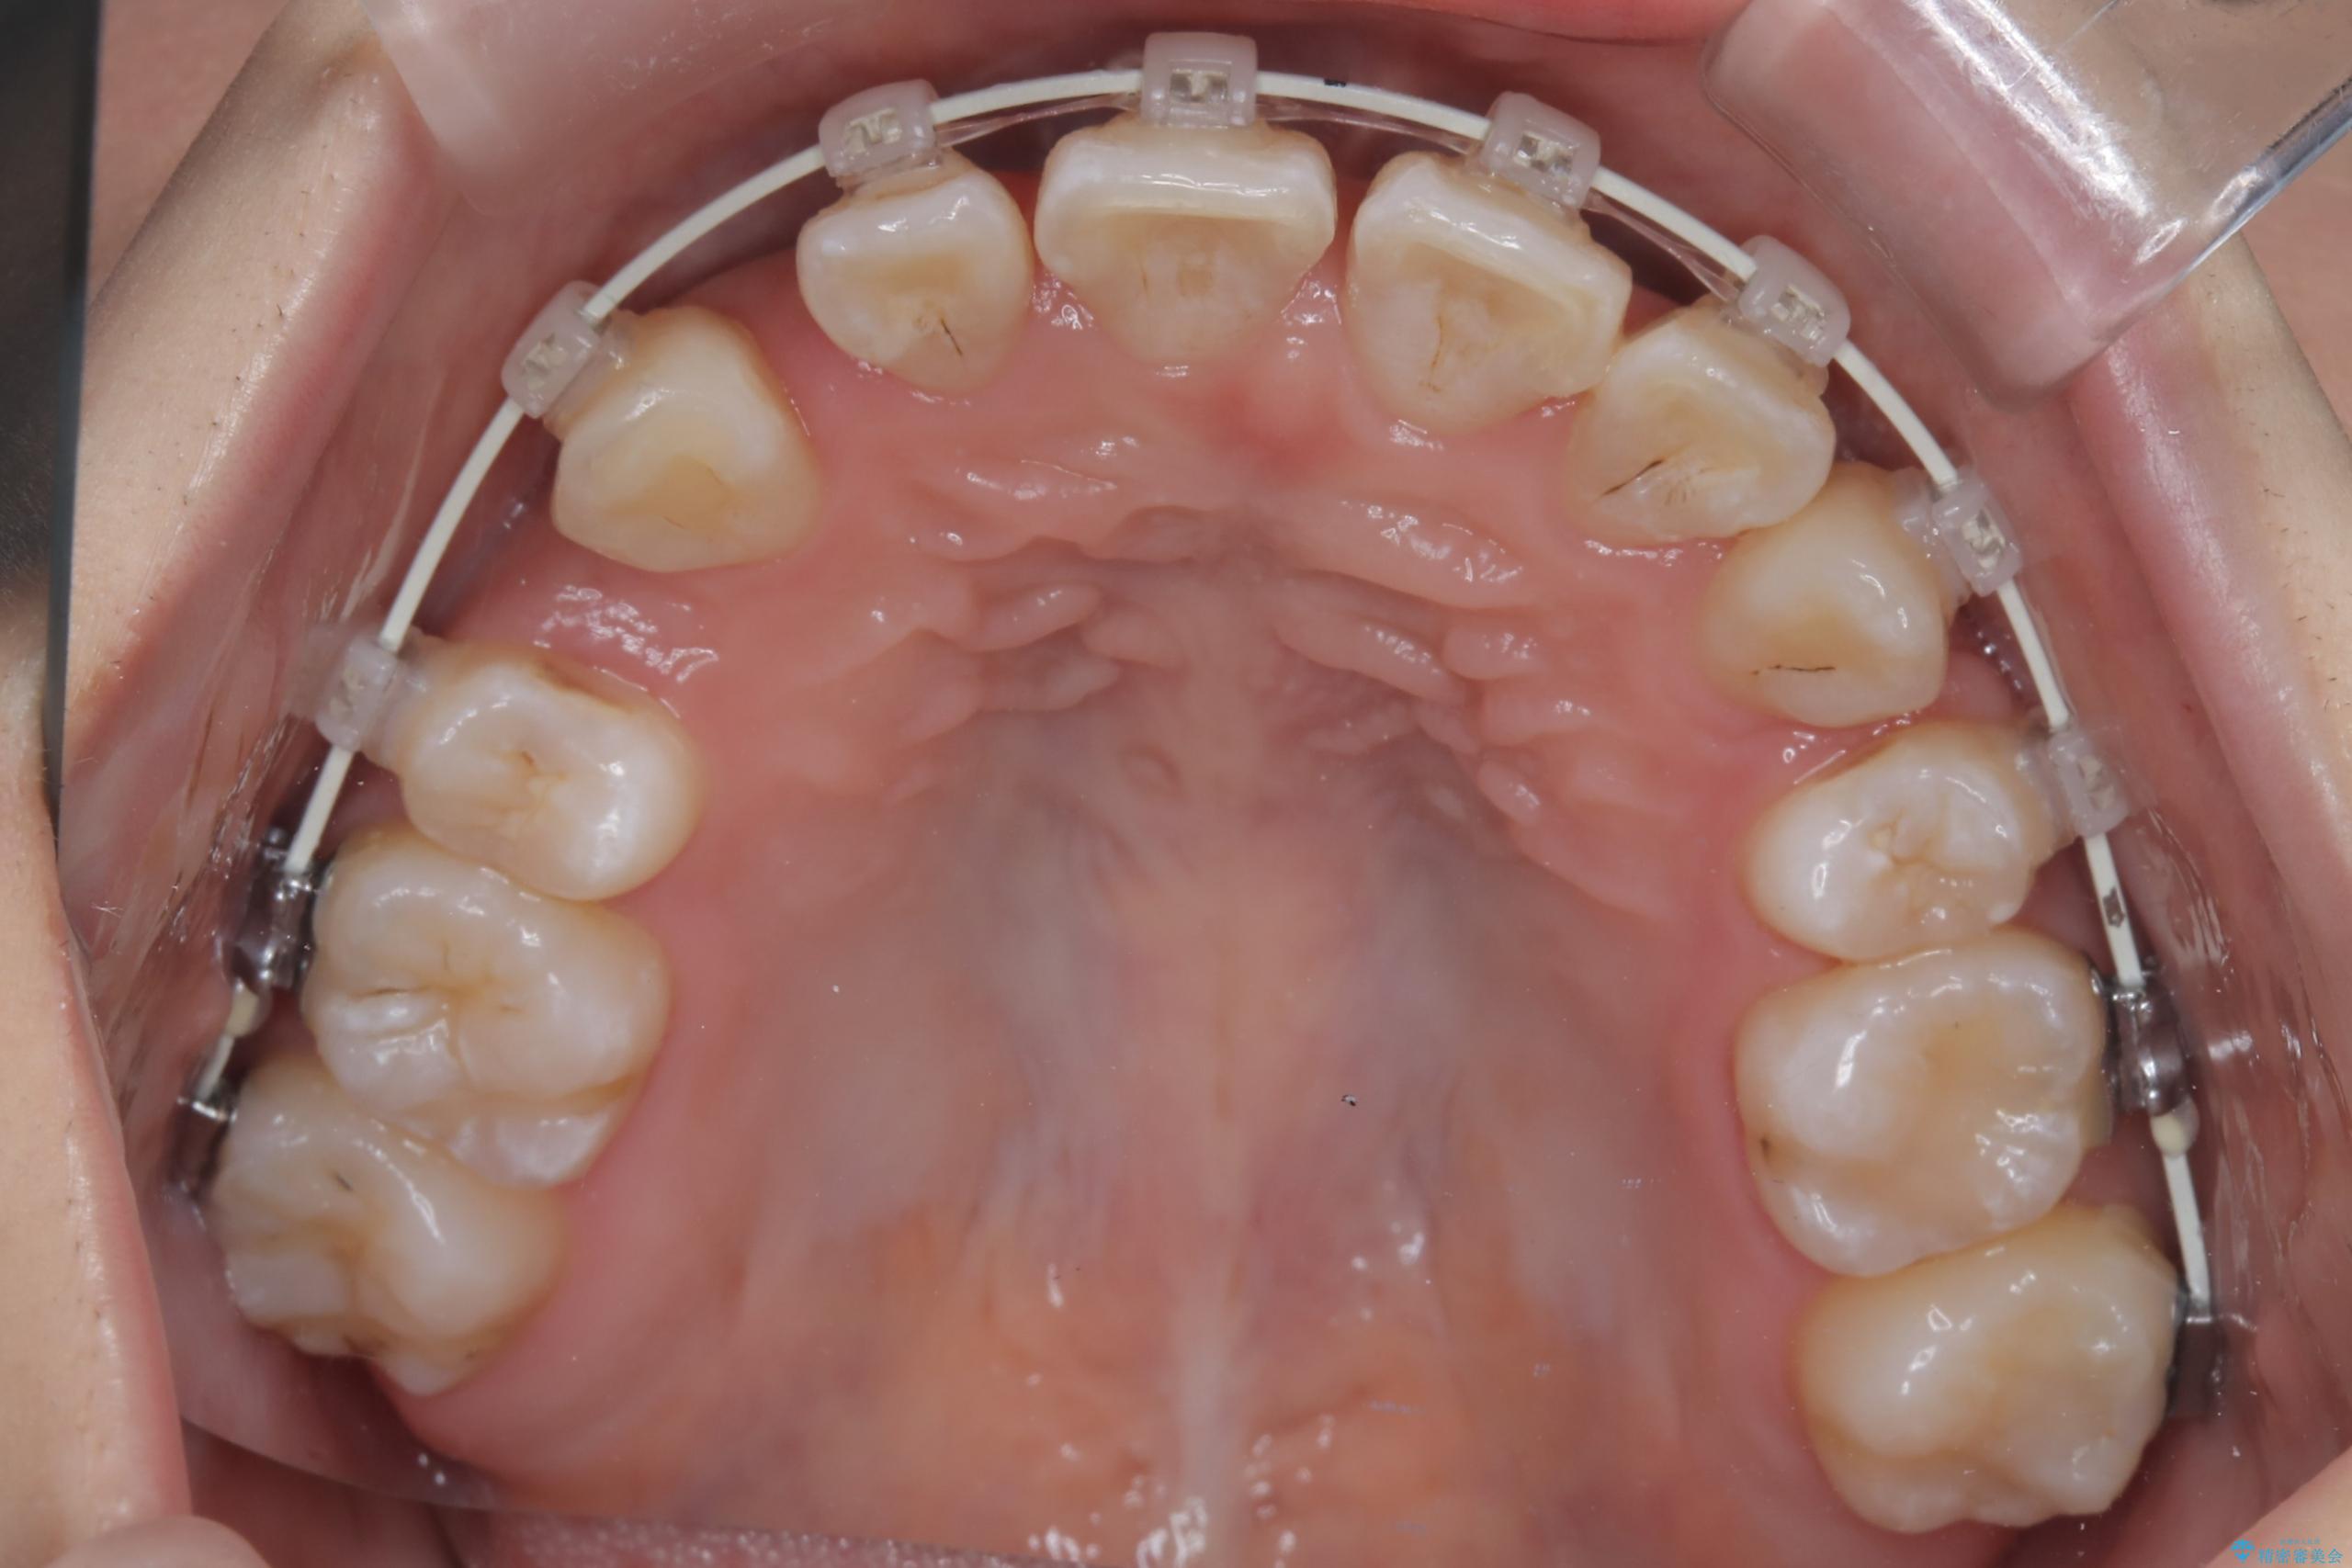

- 八重歯(叢生)と、上下の歯の中心線(正中)がずれていることを主訴にご来院されました。精密な検査の結果、歯列全体のスペースが大幅に不足しており、八重歯を正しい位置に配列し、正中のズレを改善するためには、上下左右の第一小臼歯を抜歯する必要があると診断。装置には、目立ちにくい審美ワイヤーを使用し、見た目を気にせず、機能性と審美性が完璧に整った咬み合わせを目指す治療計画を立案しました。

今回の矯正治療では、まず計画通り上下左右の小臼歯4本を抜歯し、八重歯や正中のズレを解消するための十分なスペースを確保しました。装置には、目立ちにくい白いブラケットとワイヤーを使用した審美ワイヤー矯正を採用。

八重歯: 突出していた八重歯を歯列内に誘導し、デコボコを解消しました。

正中のズレ: 歯を左右対称に移動させることで、上下の歯の中心線を正確に合わせ、顔全体のバランスも改善しました。